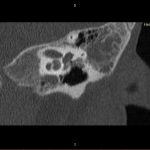

- Diagnosticul traumatismelor de bază de craniu

- Diagnosticul fracturilor:

- Complexe cranio-sinusale

- Complexe cranio-etmoidale

- Complexe cranio-orbitare

- Complexe cranio-faciale